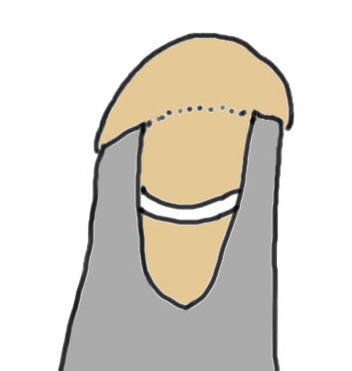

Large full thickness tear of supraspinatus and infraspinatus tendon - retracted to midhumeral head